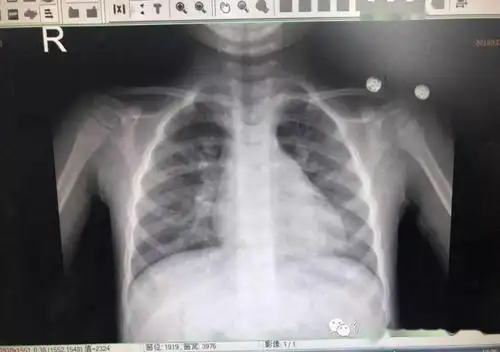

小孩得了肺炎,我们在日常中该如何护理呢? 正常胸片

(详细讲解肺炎胸片和最新病案~)

大家来看看这张小孩子 的胸片

新生儿30天得肺炎,现在在妇幼icu,这是胸片,很严重吗

读片小儿胸片